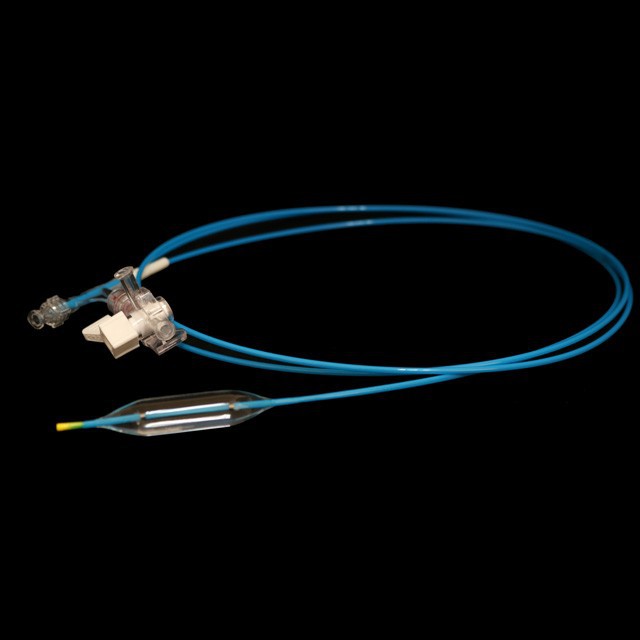

Mult ባለብዙ ክንፍ ከሚያስደስት በኋላ ቴርሜትሪክስ ደስ የሚሉ የመቋቋም ችሎታ እና ተለዋዋጭ ሽርሽር ከስራ ሰርጡ .}

The የቱቦው ምርጥ የቱቦው ተስማሚ ንድፍ ለስላሳ እና ጥሩ የመለጠጥ ችሎታ, ጠንካራ የመቋቋም ችሎታ እና ቀላል አለባበስ .

● ቅድመ-ግቤት 0 . 035 "ለስላሳ ጉርሻ እና ማርቆስ የግንባታውን ቅጥር ሽቦው ርዝመት ለመገመት ቀላል የሆነ.